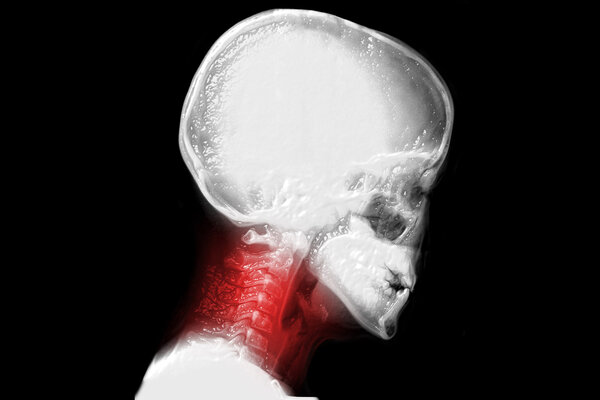

喉咙有血腥味癌症

喉咙有血腥味可能与鼻咽癌、肺癌等癌症相关,鼻咽癌与EB病毒感染等有关可伴鼻塞等症状可通过鼻咽镜等诊断,肺癌与吸烟等有关可伴咳嗽等症状可通过胸部影像学等诊断,还可能由非癌症因素如口腔疾病、上呼吸道感染、剧烈咳嗽等引起,出现时不要惊慌,年轻人可先观察处理,中老年人等高危人群应及时就医详细描述症状配合检查,癌症引起的按情况制定个性化治疗方案,非癌症因素引起的针对病因治疗。